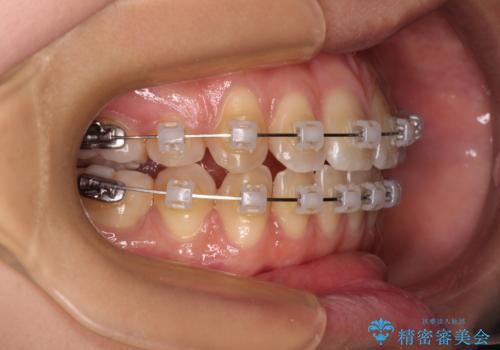

- クリアブラケット

- 上下顎前歯部の非接触(開咬)と下顎のデコボコを主訴に来院された患者様です。

右側上下と左上の小臼歯が一本ずつ少なく、さらに骨格的な左右差もあり上下の真ん中の位置がずれています。

下顎のデコボコの解消と、真ん中の位置を改善するために左下の小臼歯を抜歯することとしました。

また、開咬を改善するため臼歯部にアンカースクリューを用いて圧下する力をかけていきました。